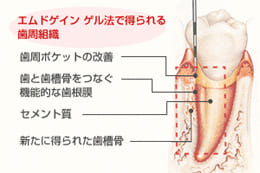

エムドゲイン法

今までの歯周病の治療は、歯石・壊死セメント質などの炎症をきたす原因物質を除去し、治癒を促すものでしたが、すでに破壊されてしまった歯周組織の再生は非常に難しいものでした。

スウェーデンで開発されたエムドゲインは、歯周外科の治療後に塗布することにより、破壊されたセメント質などの再生を図るものです。